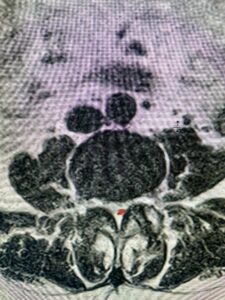

The next patient is a 56-year-old morbidly obese female who had progressive leg pain and weakness. She was over 320 lbs and did not have diabetes either. On MRI she had a massive disc herniation spanning the L3-4 and L-4 interspaces, centered behind the L4 vertebral body (Fig 3A and B). She also had an L4-5 spondylolisthesis. There were opinions that the disc emanated from the L3-4 disc space, but because of spondylolisthesis and on careful inspection of the MRI, there was a high chance the disc herniation had instead emanated from L4-5 (Fig 4). She had conservative treatment including epidurals but had worsening strength and numbness. She was scheduled electively for surgery, but then fell, and broke her ankle. She could not walk, particularly due to the pain down her leg. She was taken to the operating room urgently after she was cleared medically. She had no issues cardiologically and was taken to the operating room. The patient underwent a laminectomy that extended above the L3-4 disc space to below the L4-5 disc space. We encountered mainly centered on the left at the level of the L4 vertebral body and massive disc herniation that created a huge cavity in the lumbar canal. It was covered in an interesting thin membrane that we dissected off the disc herniation (Fig 5). Postoperatively the patient did experience significant relief of pain, but some improvement of strength. In combination with the ankle fracture and the extent of preoperative weakness, the patient required extensive rehab. The patient also developed a seroma and some wound drainage issues that were treated locally.

Fig. 3a : Sagittal T2-weighted lumbar MRI demonstrating a massive L4-5 disc herniation with superior migration behind the L4 vertebral body and taking up most of the left side of the spinal canal (red arrow) Note the slight grade one spondylothesis at L4-5 (blue dash). Notice the severe compression of the thecal sac (blue arrow) by the large left sided disc herniation (red arrow)

Fig. 3b: Axial T2-weighted lumbar MRI demonstrating severe compression of the thecal sac (blue arrow) by the large left sided disc herniation (red arrow) taking up most of the left side of the spinal canal (red arrow)